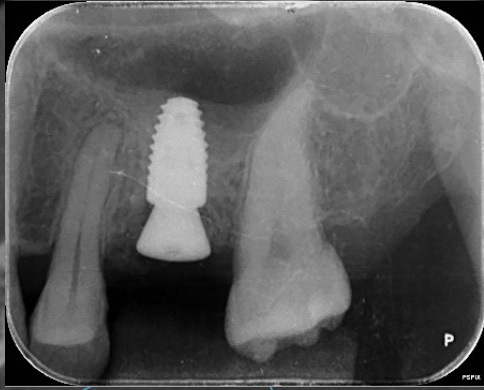

インプラントが骨に覆われている

状態の確認

デンタルX線では、インプラントが周囲骨により安定して支えられている様子を確認できます。

インプラントの長期安定には、骨の支えに加えて、清掃性と歯肉のバリアも重要です。